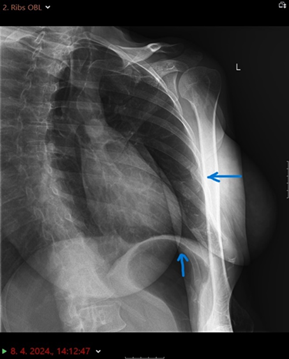

The chest X-ray posteroanterior (PA) and oblique radiograph

projection view

showed in the lateral part of the left sixth and

ninth rib, visible fractures without

major displacement of the bone fragments. There are no signs of pneumothorax.

Lung parenchyma and bronchial wall thickness were normal (Figure 1).

Figure 1. (A) Radiological image of the thorax. Chest oblique and

posteroanterior radiograph projection view

(B). The blue arrow points an visible fractures of the left sixth and ninth

ribs.